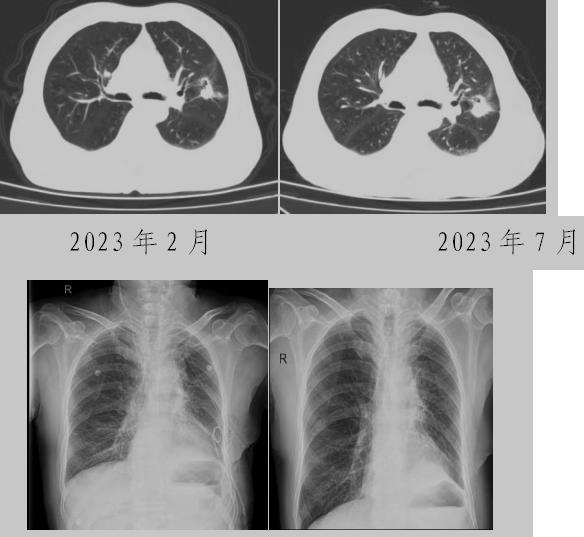

病例二:42歲的范女士,半年前體檢時(shí)發(fā)現(xiàn)雙側(cè)多發(fā)肺結(jié)節(jié),平時(shí)沒(méi)有什么不適。四個(gè)月后再次復(fù)查胸部CT,左上肺及下肺多發(fā)的磨玻璃結(jié)節(jié),其中下葉9mm的結(jié)節(jié)定為高危病灶??吹浇Y(jié)果范女士坐不住了,多方打聽(tīng)慕名找到了市二院院長(zhǎng)王瑾,經(jīng)“肺結(jié)節(jié)MDT”團(tuán)隊(duì)會(huì)診后,決定手術(shù)治療。入院后,胸外科副主任醫(yī)師薛飛詳細(xì)與范女士溝通,并利用Mimics做好了術(shù)前肺部三維重建手術(shù)規(guī)劃,打消了范女士心中的顧慮。經(jīng)過(guò)前期充分準(zhǔn)備后,歷經(jīng)1小時(shí)30分,完成“胸腔鏡下左肺上葉舌段楔切及左肺下葉背段切除術(shù)”,術(shù)后病理檢查結(jié)果確診為左肺微浸潤(rùn)性腺癌。在胸外科團(tuán)隊(duì)的悉心照顧下,患者術(shù)后恢復(fù)良好,一周后順利出院。